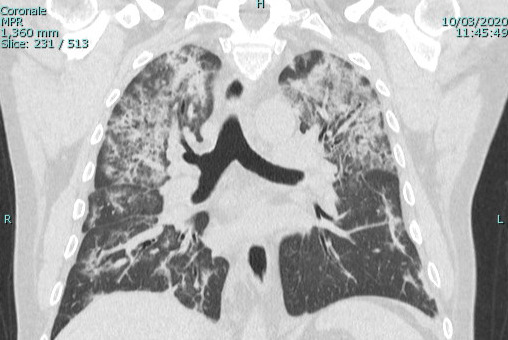

In the 33 (69.3%) of the cases with both a chest CT and a chest radiograph, the radiograph showed signs of COVID-19 (Figure 3). Most chest radiographs had non-specific findings, with the most common findings noted as hypotransparency (i.e., mild opacity in an area that should be transparent) or the radiologist documenting that the chest x-ray was consistent with COVID-19 without further detail. A total of 46 (97.8%) of the sample cases showed bilateral lung findings consistent with COVID-19 on CT. One (2.1%) patient x-ray showed only unilateral findings, with ground glass opacities being found in the left lung only. (Figure 4)